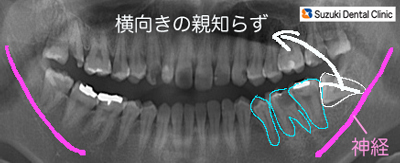

横向き親知らずのレントゲン

コラム「横向き親知らずのレントゲン」の画像